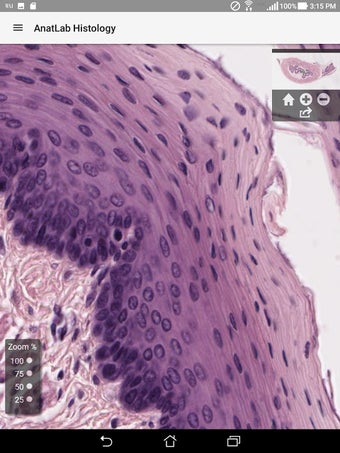

AnatLab Histology es una aplicación gratuita para Android desarrollada por Eolas Technologies Inc. que proporciona a los usuarios imágenes de diapositivas microscópicas de ultra alta resolución. Esta aplicación es una herramienta ideal para estudiantes, profesores, investigadores y el público en general. Con esta aplicación, pueden explorar el paisaje microscópico completo del cuerpo como si estuvieran mirando una colección de diapositivas reales en un microscopio físico. Tiene una función basada en la nube, la aplicación se puede acceder en cualquier dispositivo móvil Android, lo que la hace muy conveniente y accesible.

La aplicación ofrece una colección completa de imágenes de diapositivas microscópicas de histología que se pueden ver en ultra alta resolución. Las imágenes son de calidad excepcional y proporcionan una representación precisa del paisaje microscópico del cuerpo. La aplicación es fácil de usar y navegar, lo que permite a los usuarios explorar diferentes partes del cuerpo con facilidad.